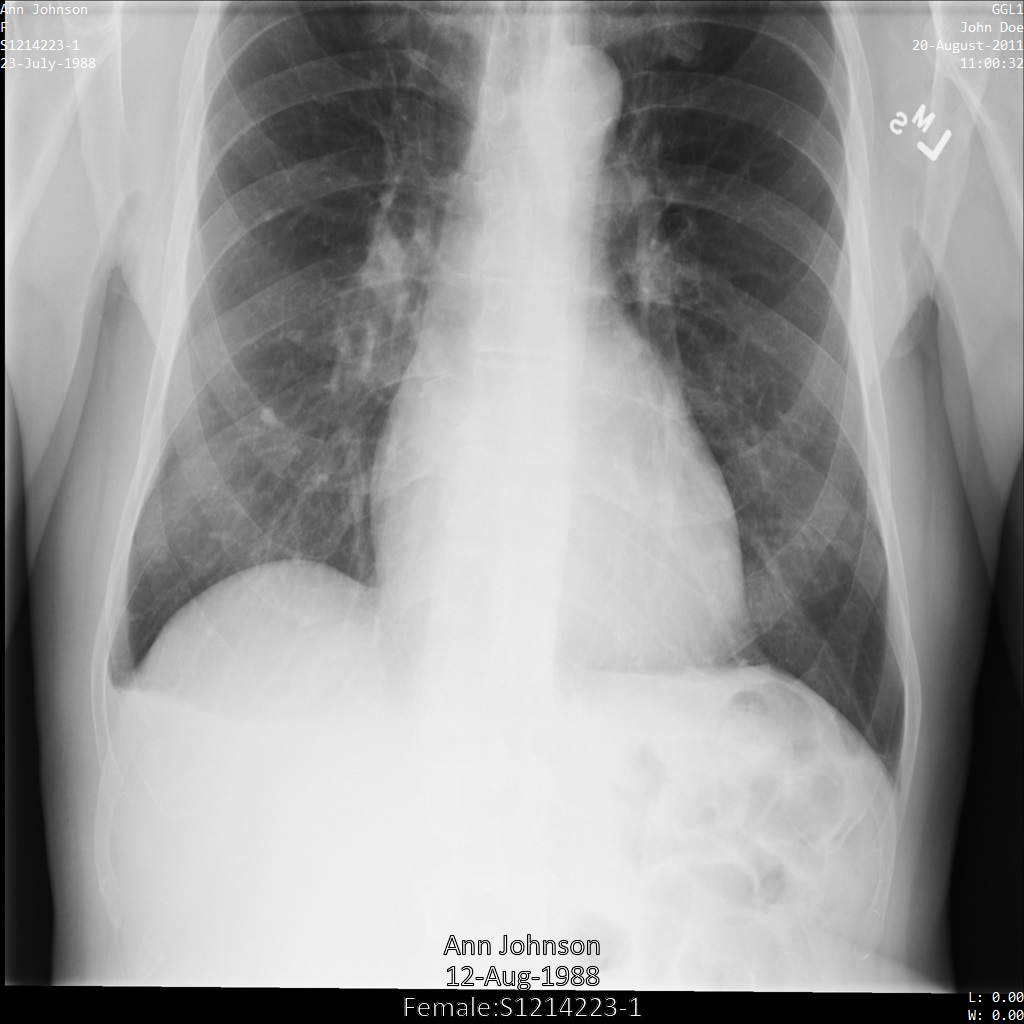

Después de enviar la imagen a la API de Cloud Healthcare mediante las opciones REDACT_ALL_TEXT y DEIDENTIFY_TAG_CONTENTS, la imagen aparece de la siguiente manera. Observa los siguientes cambios:

- Los nombres en la esquina superior izquierda y en la esquina superior derecha de la imagen se transformaron con una

CryptoHashConfig - Las fechas en la esquina superior izquierda y derecha de la imagen se transformaron con un

DateShiftConfig - Se oculta el texto grabado que aparece en la parte inferior de la imagen.

Después de enviar la imagen a la API de Cloud Healthcare mediante el perfil DEIDENTIFY_TAG_CONTENTS, la imagen aparece de la siguiente manera.

Observa los siguientes cambios:

DateShiftConfig